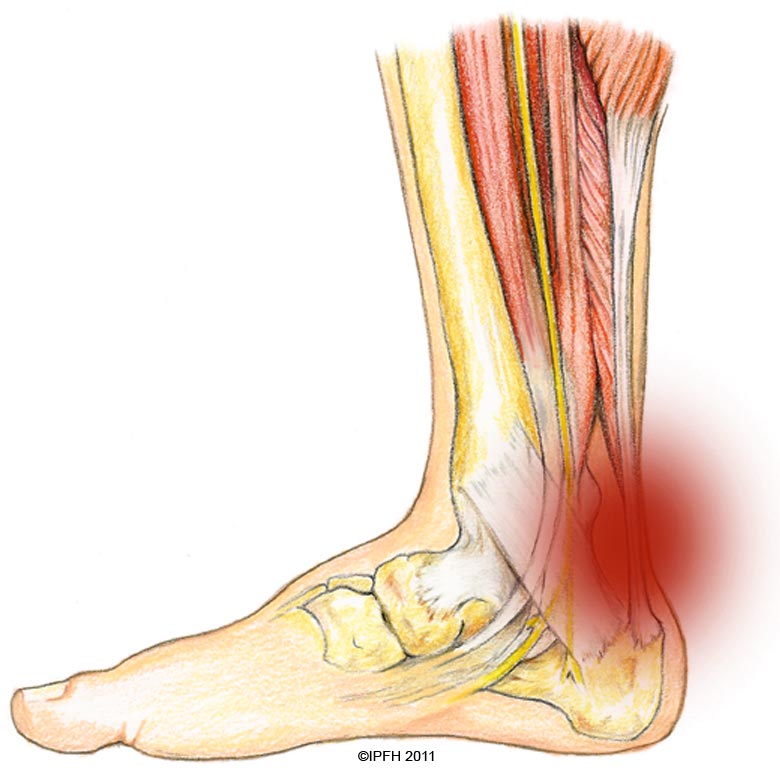

pictures of achilles tendon

Feel Better Now Series – How To Treat Achilles Tendinitis – Best home …

ACHILLES TENDINOPATHY – Step Relief Podiatry